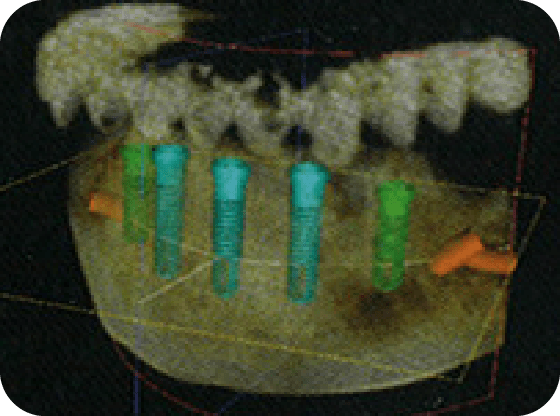

2 精密検査

最先端の設備を使った精密検査を行い、患者様の口腔内をより詳細に確認させていただき、治療が可能かどうかを診断します。より正確・安全なインプラント治療を実現するために、当院では歯科用CT(コンピューター断層撮影)を導入しています。撮影されたCT画像データはコンピュータを用いて分析し、術前の診査・診断ならびに治療計画に役立てます。